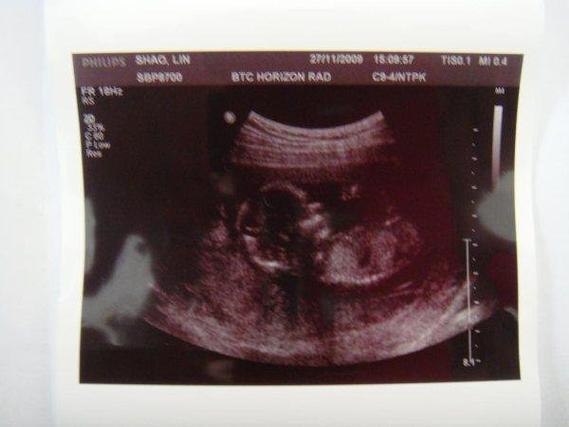

试管婴儿胎位通常较低吗?有什么影响?

我想了解一下,做试管婴儿成功怀孕后,胎儿的胎位是不是普遍会比较低呀?如果胎位低的话,这会给我和宝宝带来什么样的不良影响呢?是会增加流产风险,还是对生产过程有不好的影响之类的呢?